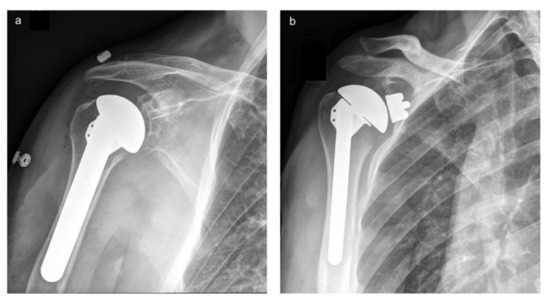

- Chin, P.Y.K.; Regan, W.D.; Plausinis, D.; Zarzour, Z.D.; Leung, F.; Sasyniuk, T.M.; Lim, B.; Sayre, E.C. Two-year results of a multi-centre, randomized controlled trial comparing a second-generation uncemented trabecular metal-backed versus cemented polyethylene glenoid component in total shoulder arthroplasty. Bone Jt. Open 2021, 2, 728–736. [Google Scholar] [CrossRef]